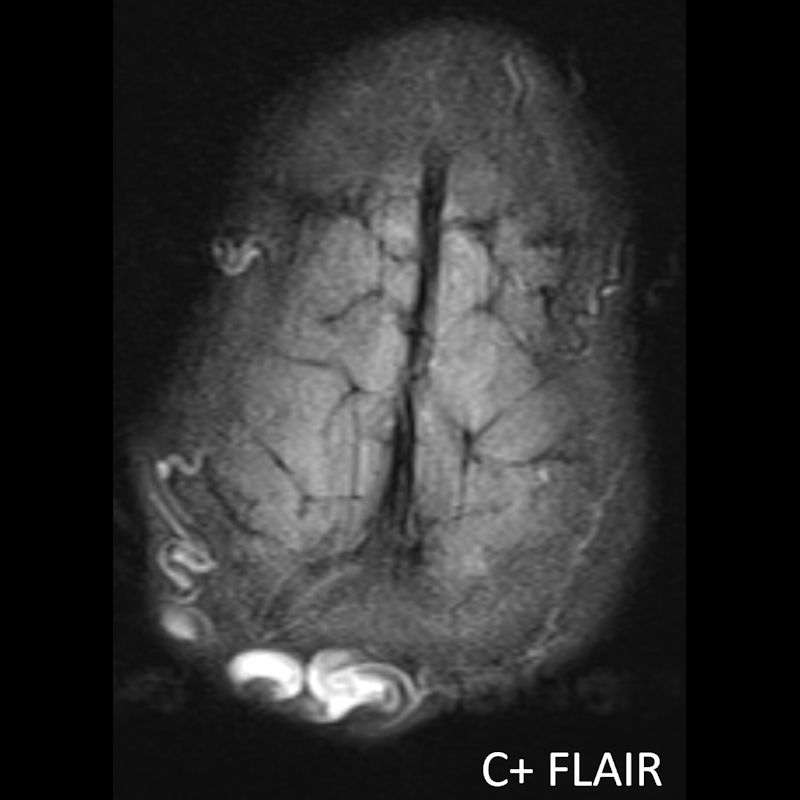

1. A) Kontrastlı FLAIR aksiyel görüntüde ve sagital T2A görüntüde vertekste orta hatta cilt altında dilate tortiyoze vasküler kollateraller (oklar). Paryetal kemikte orta hatta defekt (ok) ve defekt ile ilişkili vasküler yapıların cilt altı yumuşak dokulara uzanımı izlenmektedir.